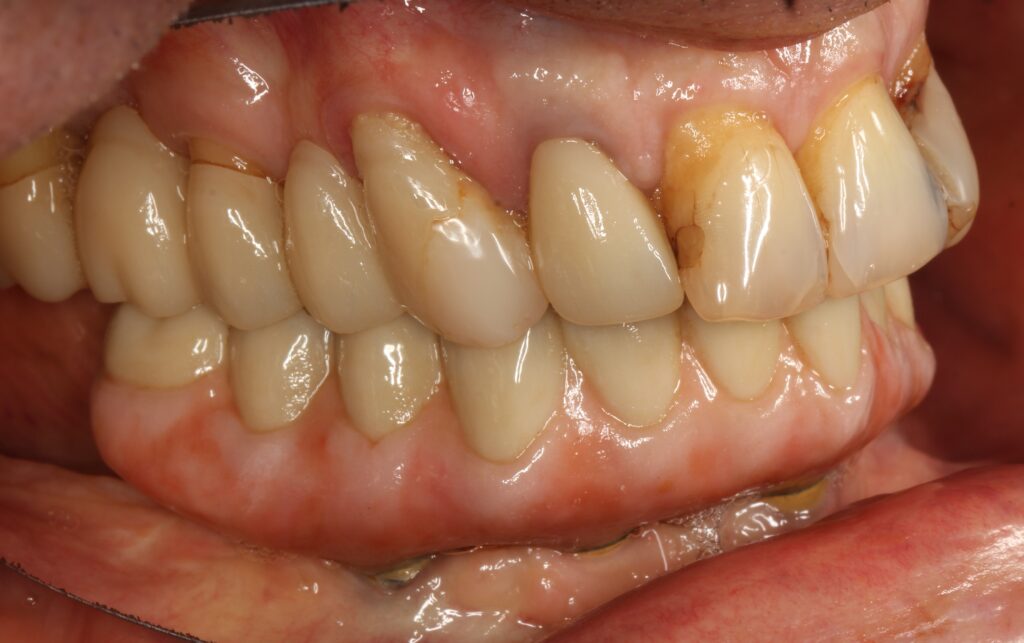

A selection of full arch fixed implant bridge patients after 5 years of wear